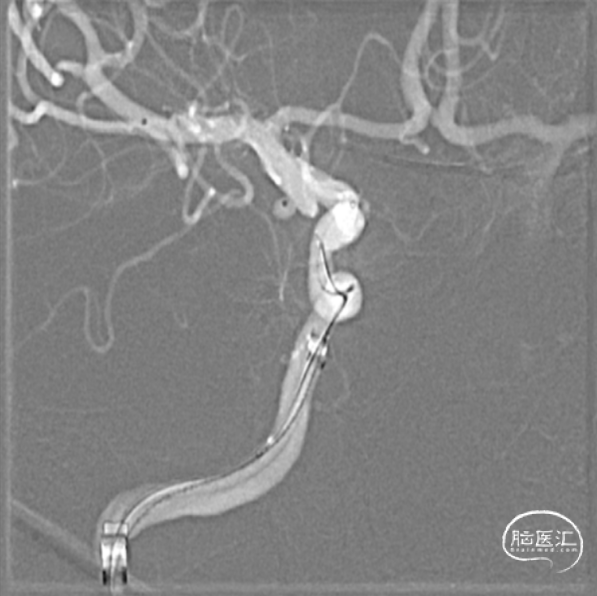

工作位造影

银蛇到位

支架微导管到位

栓塞微导管到位

穿刺右股动脉,造影证实右侧后交通动脉瘤,微小宽颈动脉瘤,5F多功能造影管带通桥银蛇6F-115直奔主题,进入右侧颈内动脉,路径图指引下微导管引导支架微导管到达预定位置,然后通过微导丝引导栓塞导管进入瘤腔,分别依次填入3D2*4cm、1.5*2cm、1*1cm三枚弹簧圈,栓塞结束后造影显示动脉瘤致密栓塞,依次撤出器械,结束手术。